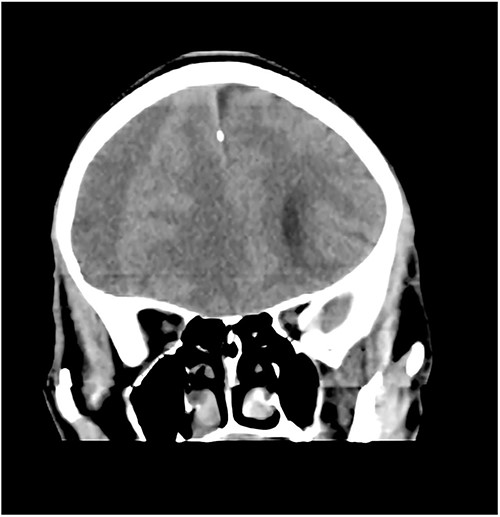

Case 3 – left isolated foot drop

A 78-year-old man with a 1-week history of headaches and dragging of the left foot. He had fallen in the bathroom 6 weeks prior to presentation. He had no other symptoms. Examination was unremarkable except for a left-sided foot drop with increased ankle jerk reflex. Brain CT done revealed a right-sided fronto-parieto-temporal CSDH (Figs 3 and 4). He had burr hole drainage and was discharged 3 days later to continue physiotherapy at home. At 4 weeks follow-up, his symptoms had completely resolved.